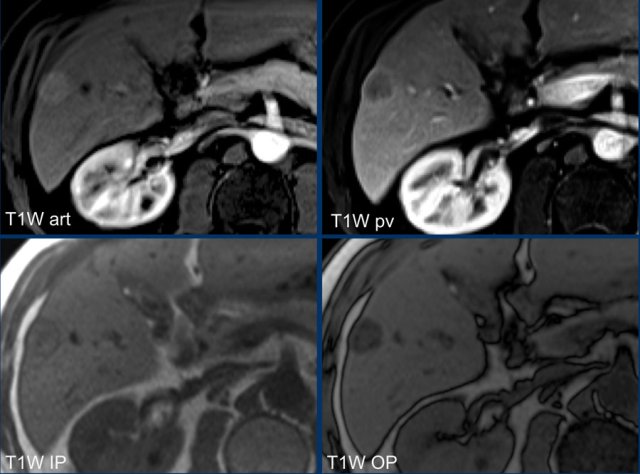

LR-M

The images show a large, heterogeneous enhancing lesion in segment II.

There is peripheral enhancement in the portal venous phase. There is high signal on T1 IP and OOP imaging and diffusion restriction.

This lesion was resected and pathology showed a mixed HCC-iCCA.